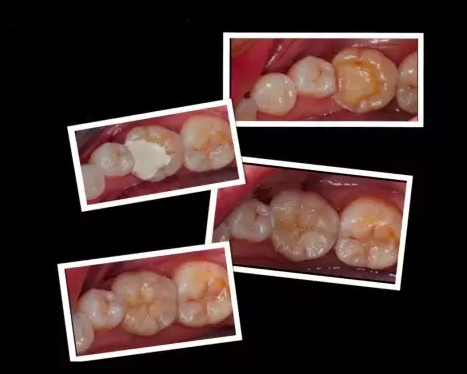

現(xiàn)在就有另外一種補(bǔ)牙方法--嵌體。想要將來(lái)不種牙,就可以選擇嵌體補(bǔ)牙!

近些年,隨著人們生活水平的提高,以及對(duì)口腔保健意識(shí)的提高,嵌體漸漸在臨床的調(diào)節(jié)中普遍開(kāi)來(lái)。同時(shí)使用過(guò)嵌體的患者,他們也漸漸認(rèn)識(shí)到了嵌體對(duì)牙齒硬組織的保留上顯現(xiàn)出來(lái)它獨(dú)特的優(yōu)勢(shì)。

嵌體和傳統(tǒng)的補(bǔ)牙不同之處是:嵌體是在口外石膏模型上由專(zhuān)門(mén)的牙科技師制作出來(lái)的,然后再由臨床醫(yī)生將其戴入患者口內(nèi),終粘固形成的。

1、因?yàn)樗恼麄€(gè)制作過(guò)程是在口外完成的,所以它還可以很好的恢復(fù)原來(lái)牙齒的外形,恢復(fù)原來(lái)牙齒的咀嚼率。而這一點(diǎn),是傳統(tǒng)補(bǔ)牙無(wú)論如何都無(wú)法比擬的。

2、嵌體的整個(gè)的制作過(guò)程中完全避免了在口腔內(nèi)部操作的干擾因素。這就使得嵌體的制作比傳統(tǒng)的補(bǔ)牙要更精細(xì)。技師在制作嵌體的時(shí)候,會(huì)控制它與牙體的彌合程度,這樣就盡可能的避免了牙齒在日后的使用中再次出現(xiàn)齲壞。

這些嵌體,在終戴如患者口內(nèi)的時(shí)候,真是的的。在使用上沒(méi)有任何的影響和不適,而且堅(jiān)固耐用。做嵌體修復(fù)的時(shí)候,好的材質(zhì)也對(duì)嵌體的修復(fù)果產(chǎn)生影響。

“嵌體,顧名思義就是是一種嵌入牙體內(nèi)部的修復(fù)方法,是為牙齒量身定做的修復(fù)體,通過(guò)黏合劑將其黏在有缺損的牙齒上?!毙旅苄“淄醚揽棋X(qián)俊霞醫(yī)生稱,由于嵌體在形態(tài)、硬度等各方面與牙齒吻合度很好,所以,它不僅解決了牙齒缺失部分容易變大的難題,也減輕了患者頻繁補(bǔ)牙的痛苦。